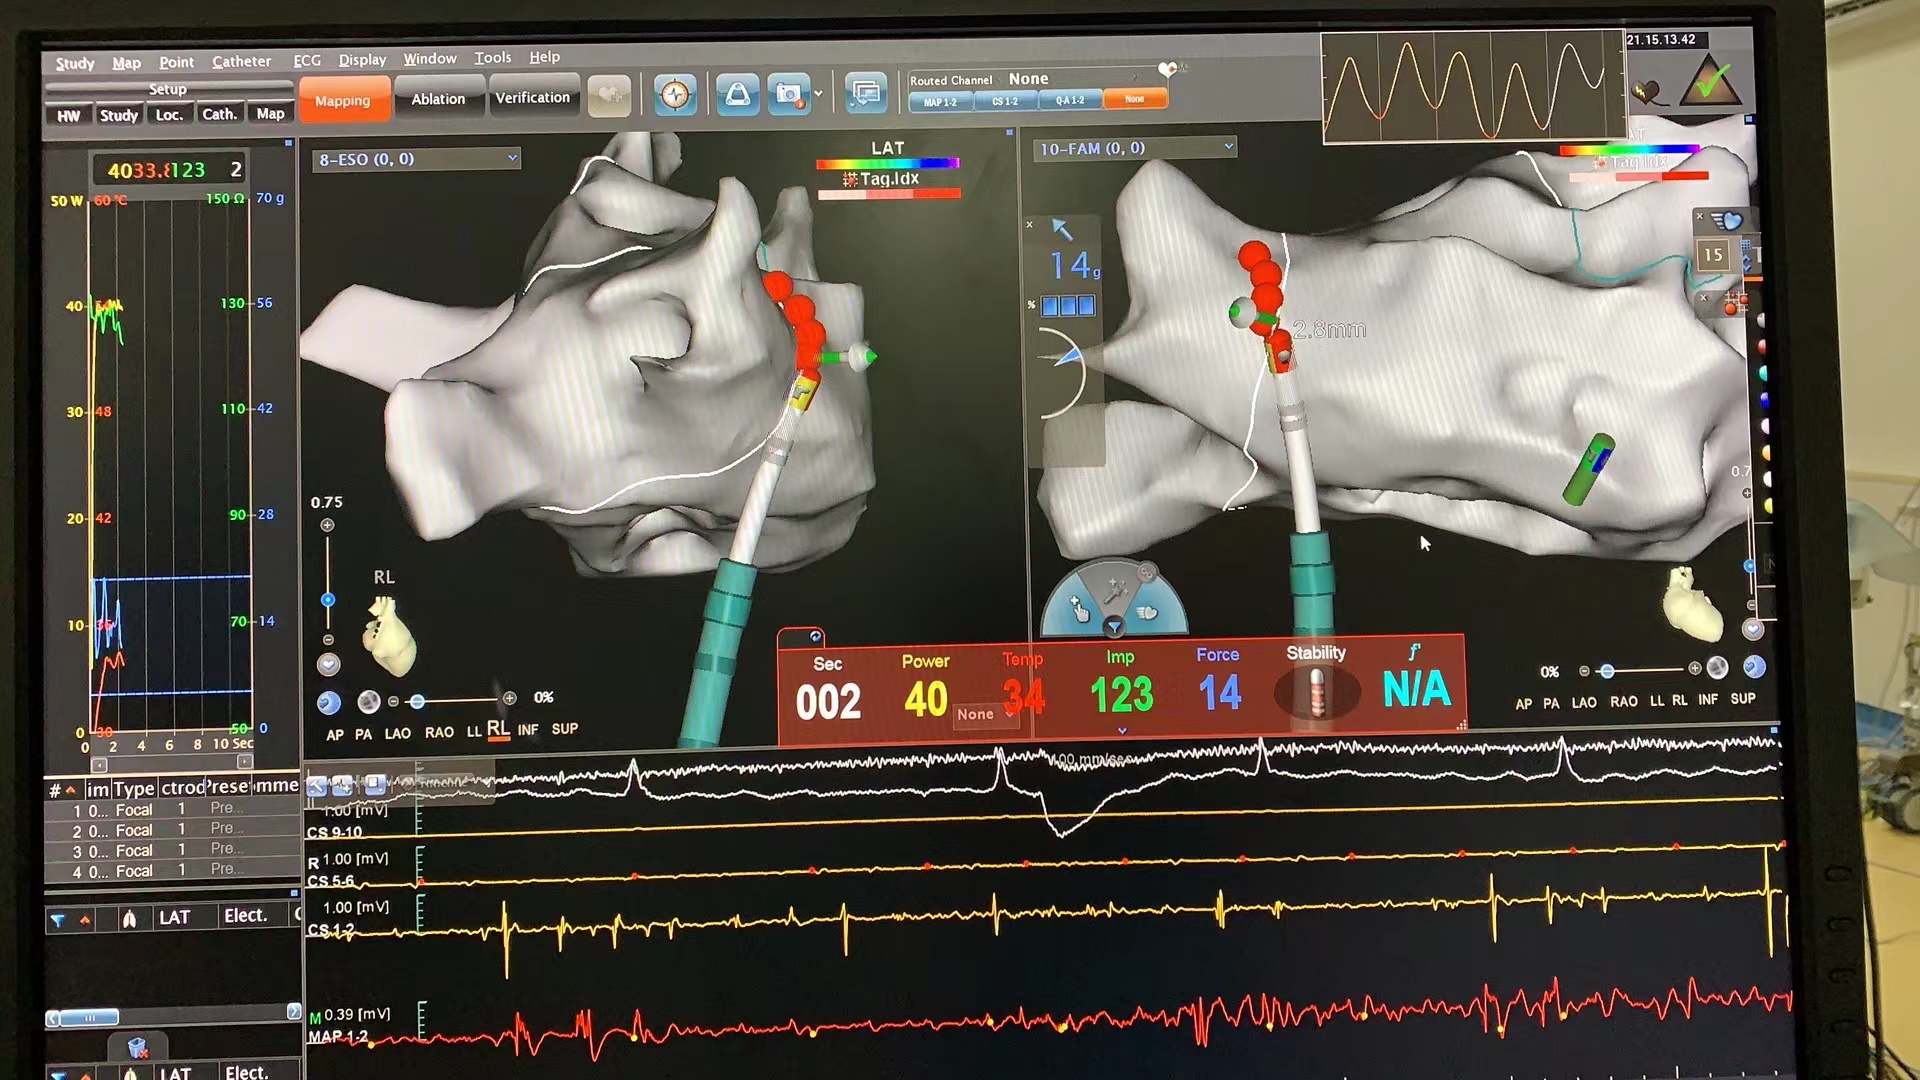

术中使用了弯型可视可调弯Vizigo鞘管,该鞘管头端有四个电极,可在Carto系统中实现实时弯型可视,在保证导管稳定贴靠的同时降低术中射线量,从而提高了房颤手术的效率及成功率。